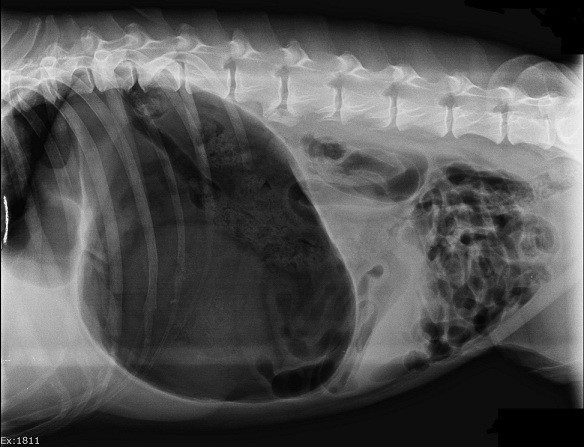

Frequently Asked Emergency Question 2

What is Canine Bloat? Bloat is more accurately called Gastric Dilatation and Volvulus (GDV), a condition where the stomach fills with gas or food and twists on its long axis. GDV can occur in any breed of dog or cat,…